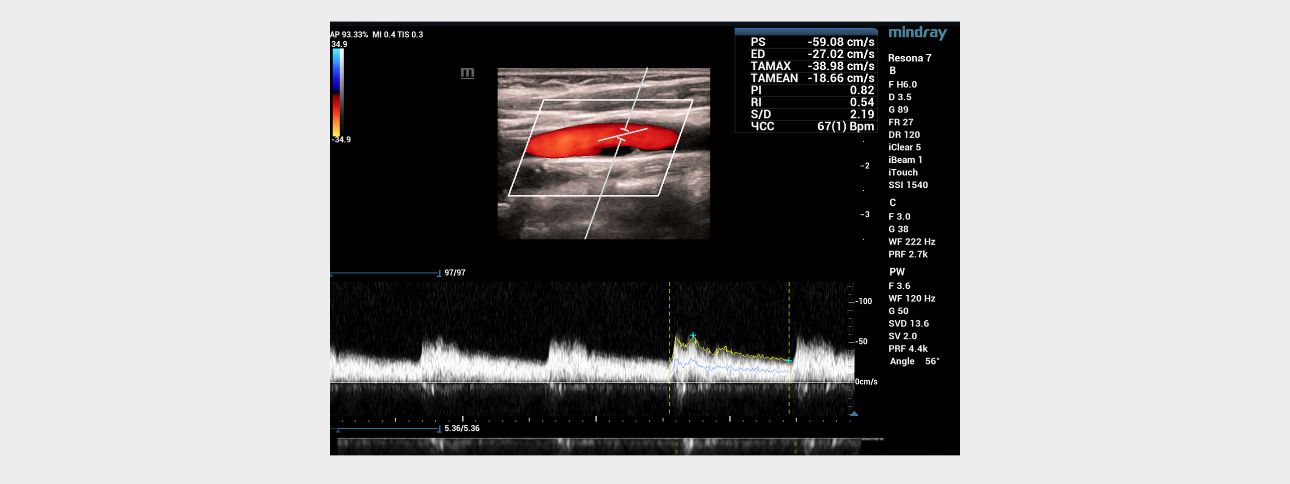

Ultrasound examination ŌĆō Doppler modes

In the mode of color Doppler mapping, in the bifurcation of the left common carotid artery along the posterior wall, an anechoic zone with a smooth surface, about 1 cm long, was visualized (Fig. 2a), which was partially filled with blue blood flow (as opposed to red in the rest of the carotid arteries) (Fig. 2b). The "aliasing" effect over the zone of detected changes was not detected. In the spectral Doppler mode, in the bifurcation of the common carotid artery, the velocity parameters of blood flow were within normal limits, no areas with local changes in hemodynamics were detected (Fig. 3).

Blood flow with normal velocity parameters (Vs=59 cm/s) is recorded above the anechoic area.

The results of ultrasound in the FSBI NCN. According to seroscale and Doppler ultrasound modes, hyperechoic linear structures were detected in the bifurcation of the common carotid arteries on both sides, with a large narrowing of the vessel lumen on the left, which could be a sign of intimal detachment and suggest dissection or a local form of fibromuscular dysplasia. An anechoic staining defect of the vessel lumen was detected behind the hyperechoic structure in the distal direction on the left in the CDK mode, which was partially filled with the color (blue) opposite to the main flow direction when changing the settings of the device and the phase of the cardiac cycle. Since it was not possible to completely paint the anechoic defect with a color stream, while not flooding the lumen of the common carotid artery with adjacent structures with color, it was impossible to exclude the presence of an atherosclerotic plaque in a typical place of its formation with a tire visualized in its proximal part or, but less likely, a parietal thrombus. The absence of an increase in the rate of blood flow and local changes in hemodynamics indicated the hemodynamic insignificance of structural changes in the carotid arteries on both sides.